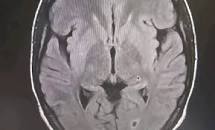

وكالة السواحل للأنباء(نواكشوط): قال الجيش الموريتاني، إن مختلف الحالات المستعجلة في مستشفيات العاصمة نواكشوط، تسجل يوميا أكثر من عشرين حالة جلطة دماغية.

وأضاف في منشور له، إن هذا العدد المسجل في مستشفيات العاصمة لوحدها، يجعل الجلطات الدماغية، مشكلة من مشاكل الصحة العمومية في البلاد.